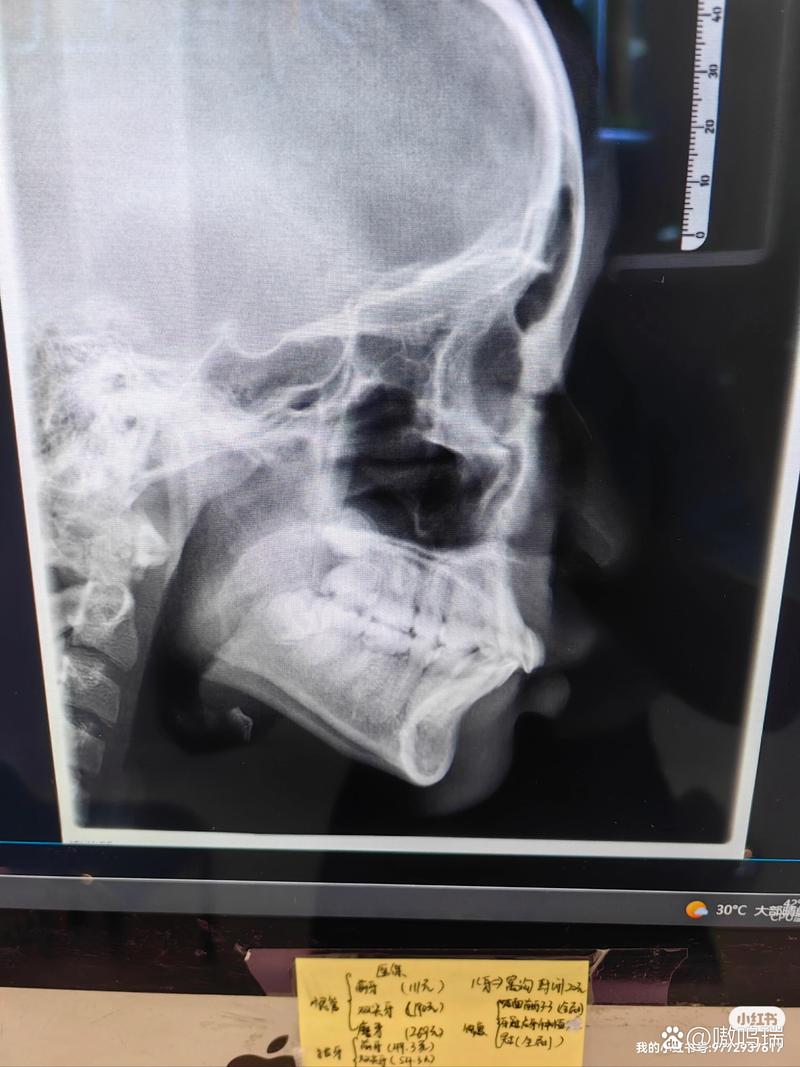

传统矫正检查依赖全景片(曲面断层片)和头颅侧位片,但这两种影像存在局限性:全景片是二维重叠影像,无法清晰显示牙根形态、颊舌侧骨板厚度及邻牙关系;头颅侧位片主要用于测量骨骼和软组织角度,对牙根位置和骨量细节显示不足,而CT通过三维重建,能精准呈现以下关键信息,为矫正提供“导航地图”:

- 颌骨与关节分析:评估颌骨发育情况(如上下颌骨大小、位置关系)、颞下颌关节(TMJ)形态,排除骨性畸形或关节疾病,避免矫正加重关节问题。